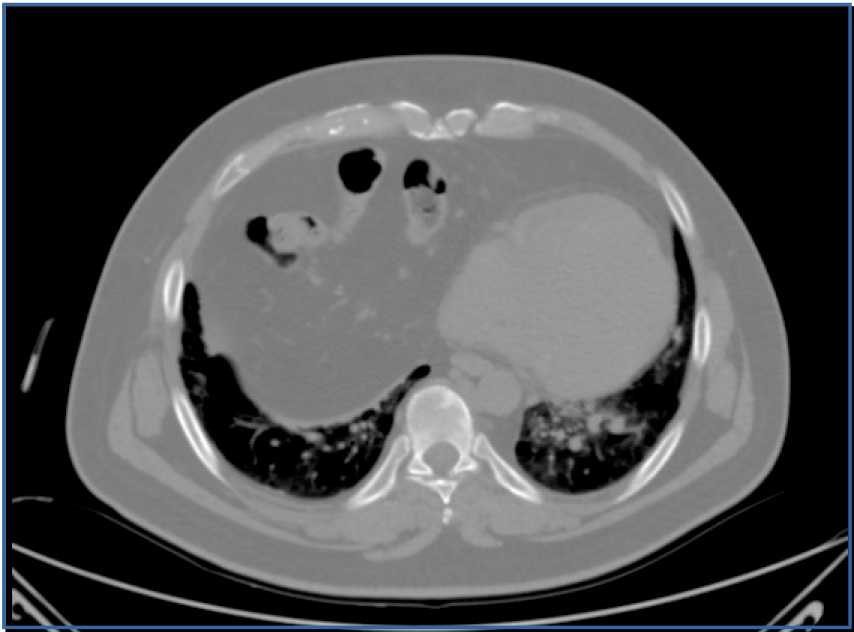

Pringle Maneuver and Blood Loss in the Surgical Treatment of Liver Hemangioma (Lh)

E. Nikolaev1*, N. Nikolov1, D. Kostov1, N. Vladov2, I. Takorov3, V. Mutafchiiski4, M. Valcheva1, I. Mircheva5

Introduction: Regardless of the type of surgical intervention to remove LH, massive blood loss remains the “Achilles heel”. Therefore, the preventive imposition of a tourniquet on the hepatoduodenal ligament (PM) should be performed in all patients without exception, but without tightening...

Resection or Enucleation for Liver Hemangioma

Introduction: Hemangiomas are the most common benign tumors of the liver. There are two main methods for surgical treatment of hepatic hemangiomas: liver resections of different sizes and enucleation. To date, there is no consensus on the surgical treatment of benign liver tumors, including hemangiomas...